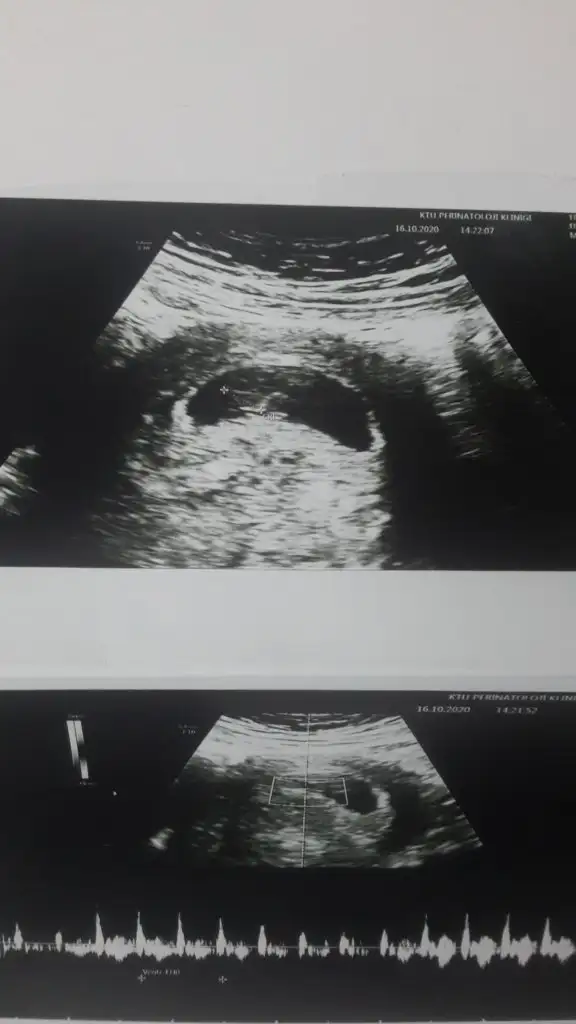

Doktorum 13+6 da kesin yüzde 100 erkek bebek pipisi var dedi 30 saniye sürdü ultrasona bakması. Ozel hastane ve sanirim doktor deneyimli. Bu saatten sonra kız olma durumu olmaz değil mi? Daha fazla sasirmak istemiyorum cunku kiz hissediyorduk...

Ultrasona bakar bakmaz cinsiyeti söyledi 13. hafta erken mi diye merak ediyordum yüzde 100 demesi için

Erkek canım pipisi yukarı doğru bizimkini 10. Haftada söylemişti doktor ve hâlâ aynı özel hastanedeki aletler biraz daha iyi oluyor o yüzden net görüntüleyebiliyorlsr

Bence kız olma ihtimali var çıkıntısı dik değil poposu ile paralel duruyor

16.haftada baska doktora gittim ve cinsiyeti bildiğimi söylemedim. Su an bacaklari kapalı ama duruşundan ve kemik yapısından erkek oldugunu tahmin ediyorum dedi ve birkac dakika sonra ultrason sırasında hareker ederken pipisini de gordum eminim erkek dedi.